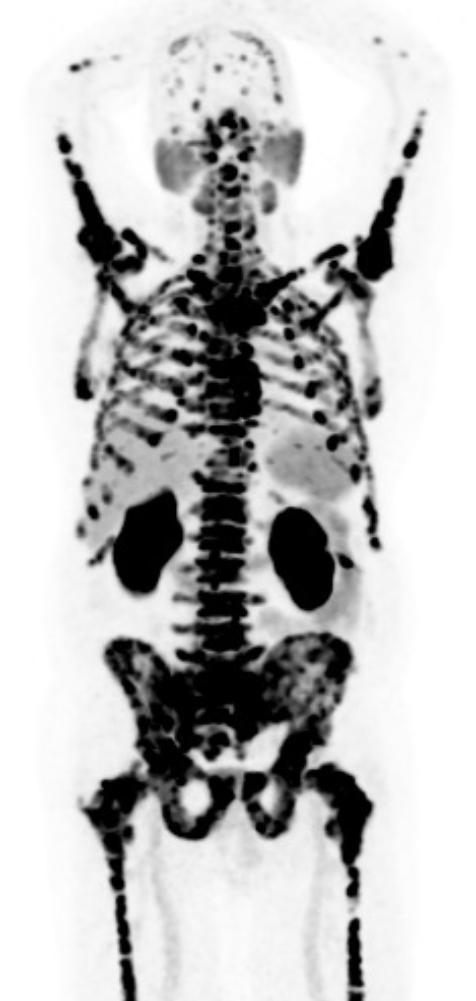

Le foie, les reins, la rate, les glandes salivaires et lacrymales, le duodénum et l’intestin grêle ainsi que la vessie sont des structures normalement visualisées lors d’un TEP au Ga68-PSMA. (Figure 2)

Aux figures 3 et 4, nous pouvons voir le même patient en TEP Ga68-PSMA et TEP F18-FDG avant le début des traitements. Sur la figure 5, nous avons le même patient environ 3 mois après la fin de ses 6 cycles de traitements.